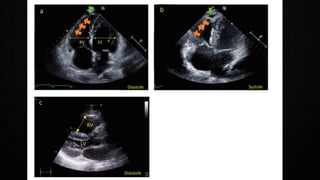

ECHOCARDIOGRAPHY IN PE

• Manifestations of RV pressure overload and dysfunction

• RV dilatation seen in >25% of patients with PE on TTE and is useful for risk stratification

of the disease

• 60/60 Sign : combination of a pulmonary ejection acceleration time (measured in the RV

outflow tract) of <60ms AND a peak systolic tricuspid valve gradient of <60mmHg

• McConnell’s sign : depressed contractility of the RV free wall when compared to the RV

apex

• Finding present only in 12-20% of unselected PE patients

• Decreased tricuspid annular systolic plane excursion (TAPSE) may also be seen in PE

• Mobile right heart thrombi (in up to 18% of PE in the ICU) essentially confirm the

diagnosis of PE and associated with high mortality rates

• Echo is not mandatory as a part of workup in hemodynamically stable patients with PE

• BUT in suspected high-risk PE, absence of echocardiographic signs of RV overload

practically excludes PE as the cause of hemodynamic instability. Can give a pointer

towards the differential diagnosis of the actual cause of shock

• Conversely, in a hemodynamically compromised patient with suspected PE, unequivocal

signs of RV pressure overload such as the McConnell’s sign or the 60/60 sign justify

emergency reperfusion treatment for PE if immediate CTPA is not feasible in a patient

with high clinical probability and no other obvious causes for RV pressure overload.